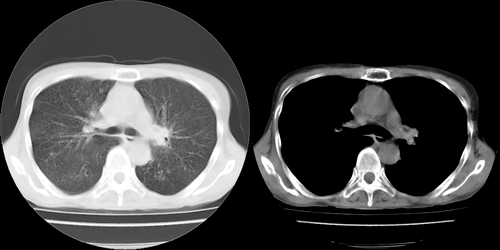

以下是引用lihuuuu在2006-7-18 18:16:00的发言:[br]支持肺结核诊断[br]本病例符合结核“三多”“三少”特征(多病灶、多形态、多钙化、少肿块、少堆积、少增强)中的前五个特征,另外左下叶背段有不张样改变-考虑伴有支气管内膜结核所致段不张。

以下是引用yang4132在2006-7-18 10:04:00的发言:[br]两肺多发 多形态病变,部分半纤维条索和斑点壮钙化,胸膜肥厚粘连,考虑结核。